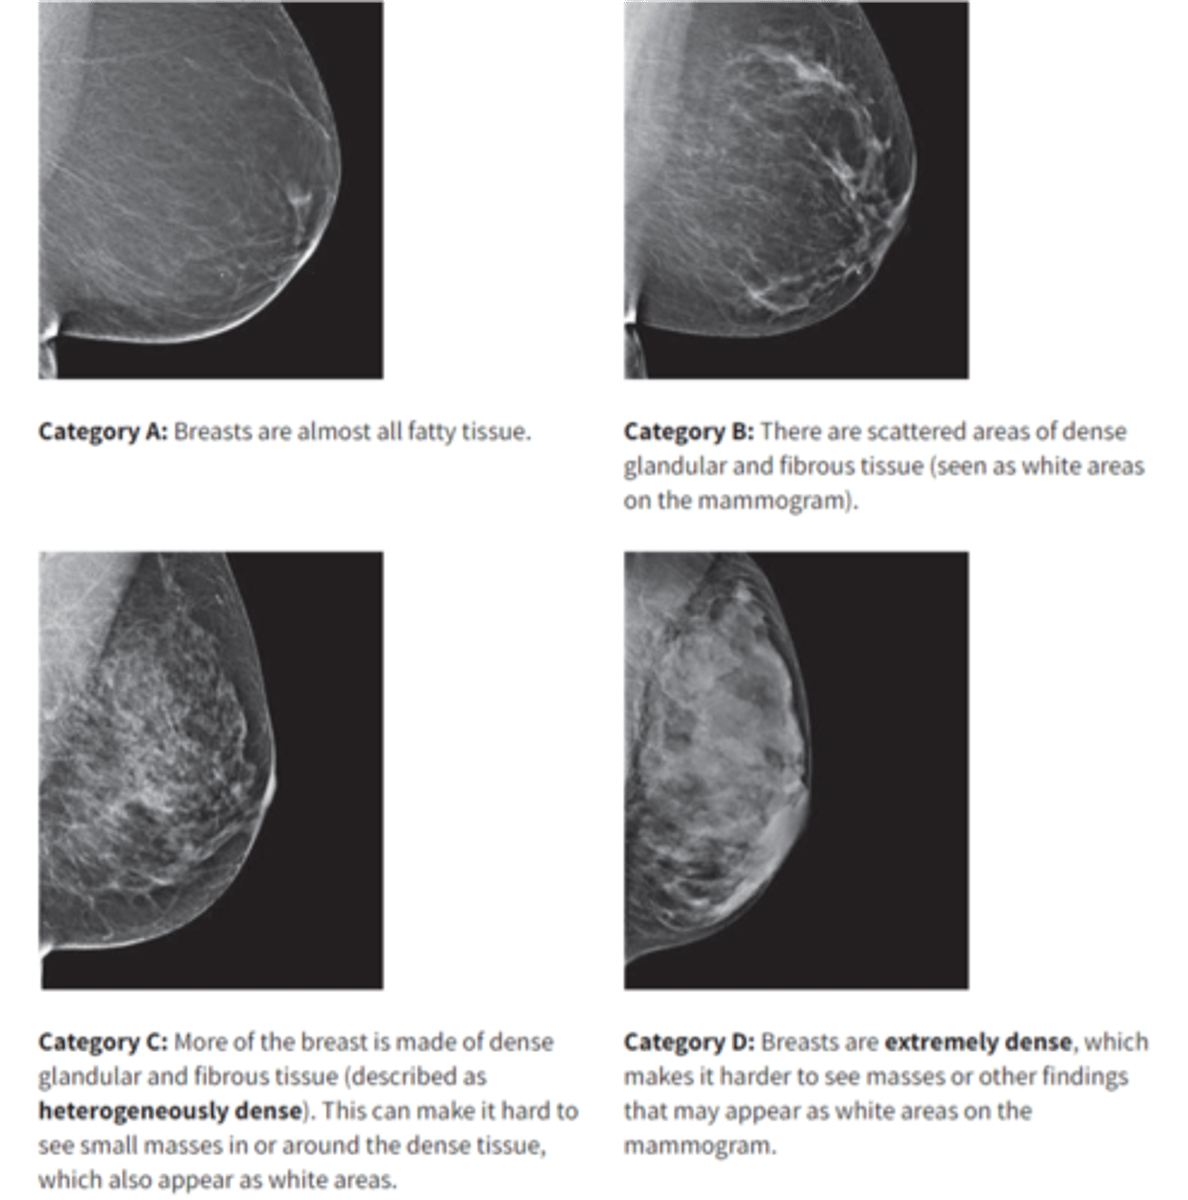

what are the BI-RADS categories?

A- Almost entirely fatty

B- Scattered areas of fibroglandular density

C- Heterogeneously dense

D- Extremely dense

Increased breast density is known to increase breast cancer risk in what two ways?

1. As an independent risk factor

2. By obscuring small findings